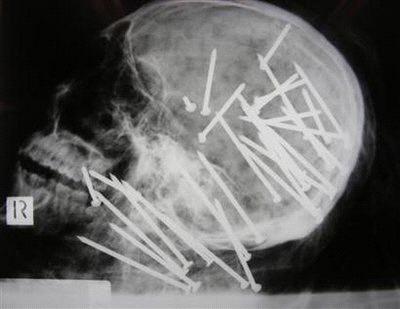

Chinese man shot 34 times in head with nail gun

Ammon News - AMMONNEWS (AP) - SYDNEY – Australian police appealed to the public Friday for help in solving the gruesome killing of a Chinese man who was shot 34 times in the head and neck with a nail gun before being dumped in a river.

New South Wales state police on Friday asked the public to provide any information they may have about the case, releasing graphic X-ray images of the 27-year-old's skull to highlight the brutality of the crime.

"In 36 years, I've never seen a murder of this nature," Homicide Squad Superintendent Geoff Beresford told reporters. "It's a particularly brutal and vicious murder and hence the reason we are seeking information from the public."

The 34 nails were found during a post-mortem examination of Liu's body, and were located mainly in his skull. They were fired from an 85 mm nail gun at close range, Beresford said. Police have not recovered the weapon.

Photo: An X-ray shows multiple nails embedded of the skull of 27-year-old Chen (Anthony) Liu that homicide squad detectives allege were fired from a high-powered nail gun in this police handout image made available April 24, 2009. REUTERS/New South Wales Police/Handout